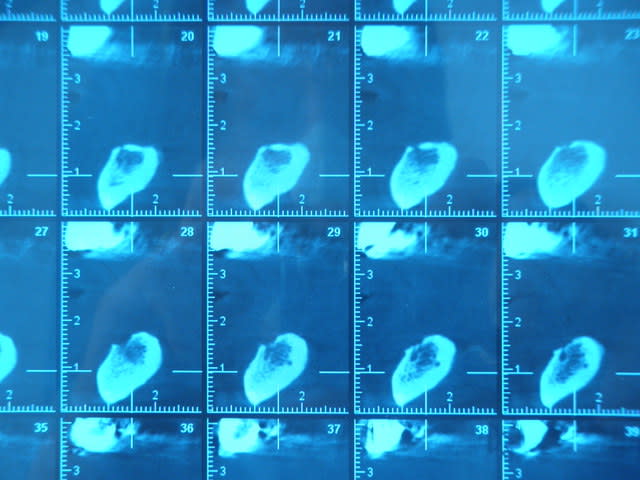

je relance ce sujet en vous demandant si l'image de gorge linguale sur les coupes correspond au passage de l'artère linguale et si c'est le cas implanteriez vous??

en espérant que les images passent bien

Il s'agit plutôt du nerf incisif. Il faut éviter de le sectionner ou de le toucher car sensibilité définitive.

artère linguale dans la mandibule => non, dans la langue par définition.

nerf incisif => oui possible, le sectionner n'a pas de conséquence chez un édenté total. incidence sur la sensibilité dentaire. mais je crois qu'on est bon.

de toute façon si on veux des implants ici il faut souvent passer au travers.

après tu peux avoir de petits rameaux artériels perforants en provenance de l'artère sublinguale.